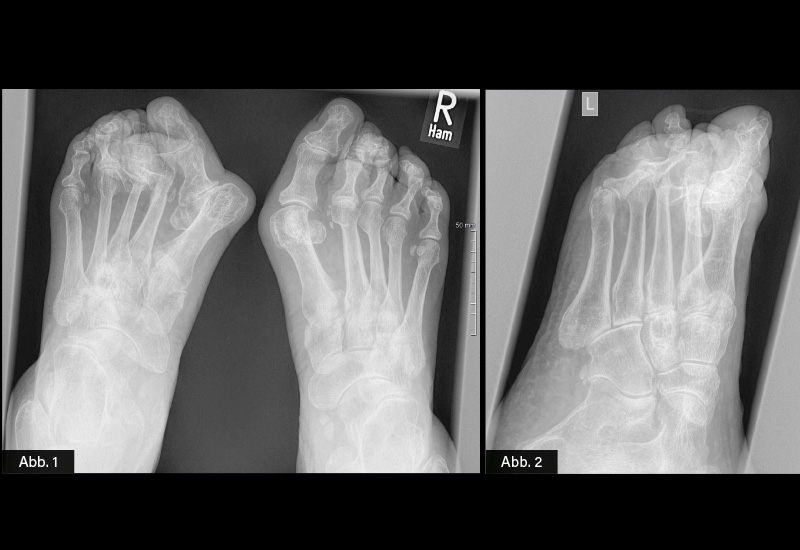

KLINISCHER BEFUND: 163 cm, 58 kg. Gelenkstatus: Keine peripheren synovitischen Schwellungen. Hallux valgus-Fehlstellung bds., ausgeprägt links mit aufgebrauchtem Quergewölbe und plantar druckschmerzhaften Metatarsalköpfchen D2-D4.

BILDGEBENDE DIAGNOSTIK:

Röntgen (siehe Abbildung)

DIAGNOSE: Hallux valgus-Fehlstellung bds., linksbetont mit Luxation und Subluxationsstellung

- Röntgen (Standard): Meist als dorso-plantare Aufnahme im Stehen (Belastung), um Ausmaß und Winkel der Fehlstellung zu bestimmen (z. B. Hallux-valgus-Winkel, Intermetatarsalwinkel)

Röntgen hilft zudem, Begleiterkrankungen (z. B. Arthrose, Luxationen der Kleinzehen) zu erfassen.